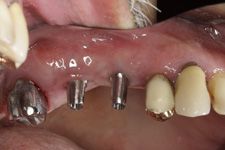

V případě chybění většího počtu zubů v postranních úsecích čelistí je možné ošetření pomocí implantátů, které nahradí ošetření pomocí snímacích náhrad kotvených na zbývajících zubech nebo patře.

Podmínkou je opět dostatečné množství kosti.

Protetické řešení může být pomocí můstku, který je kotvený na implantátech nebo pomocí jednotlivých korunek na implantátech.

V zásadě je možné do těchto můstků zařadit i přirozené zuby, zejména pokud je potřeba tyto zuby ošetřit proteticky

- korunkami. Korunky nebo můstky mohou být na implantáty nacementovány nebo přišroubovány.

Zdravé zuby zůstanou zachovány a přitom náhrady jsou pevné, jako na vlastních zubech